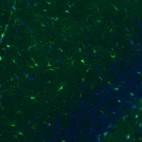

Immunohistochemistry analysis in human cerebral cortex and kidney tissues using AMAb91038 antibody. Corresponding S100B RNA-seq data are presented for the same tissues.